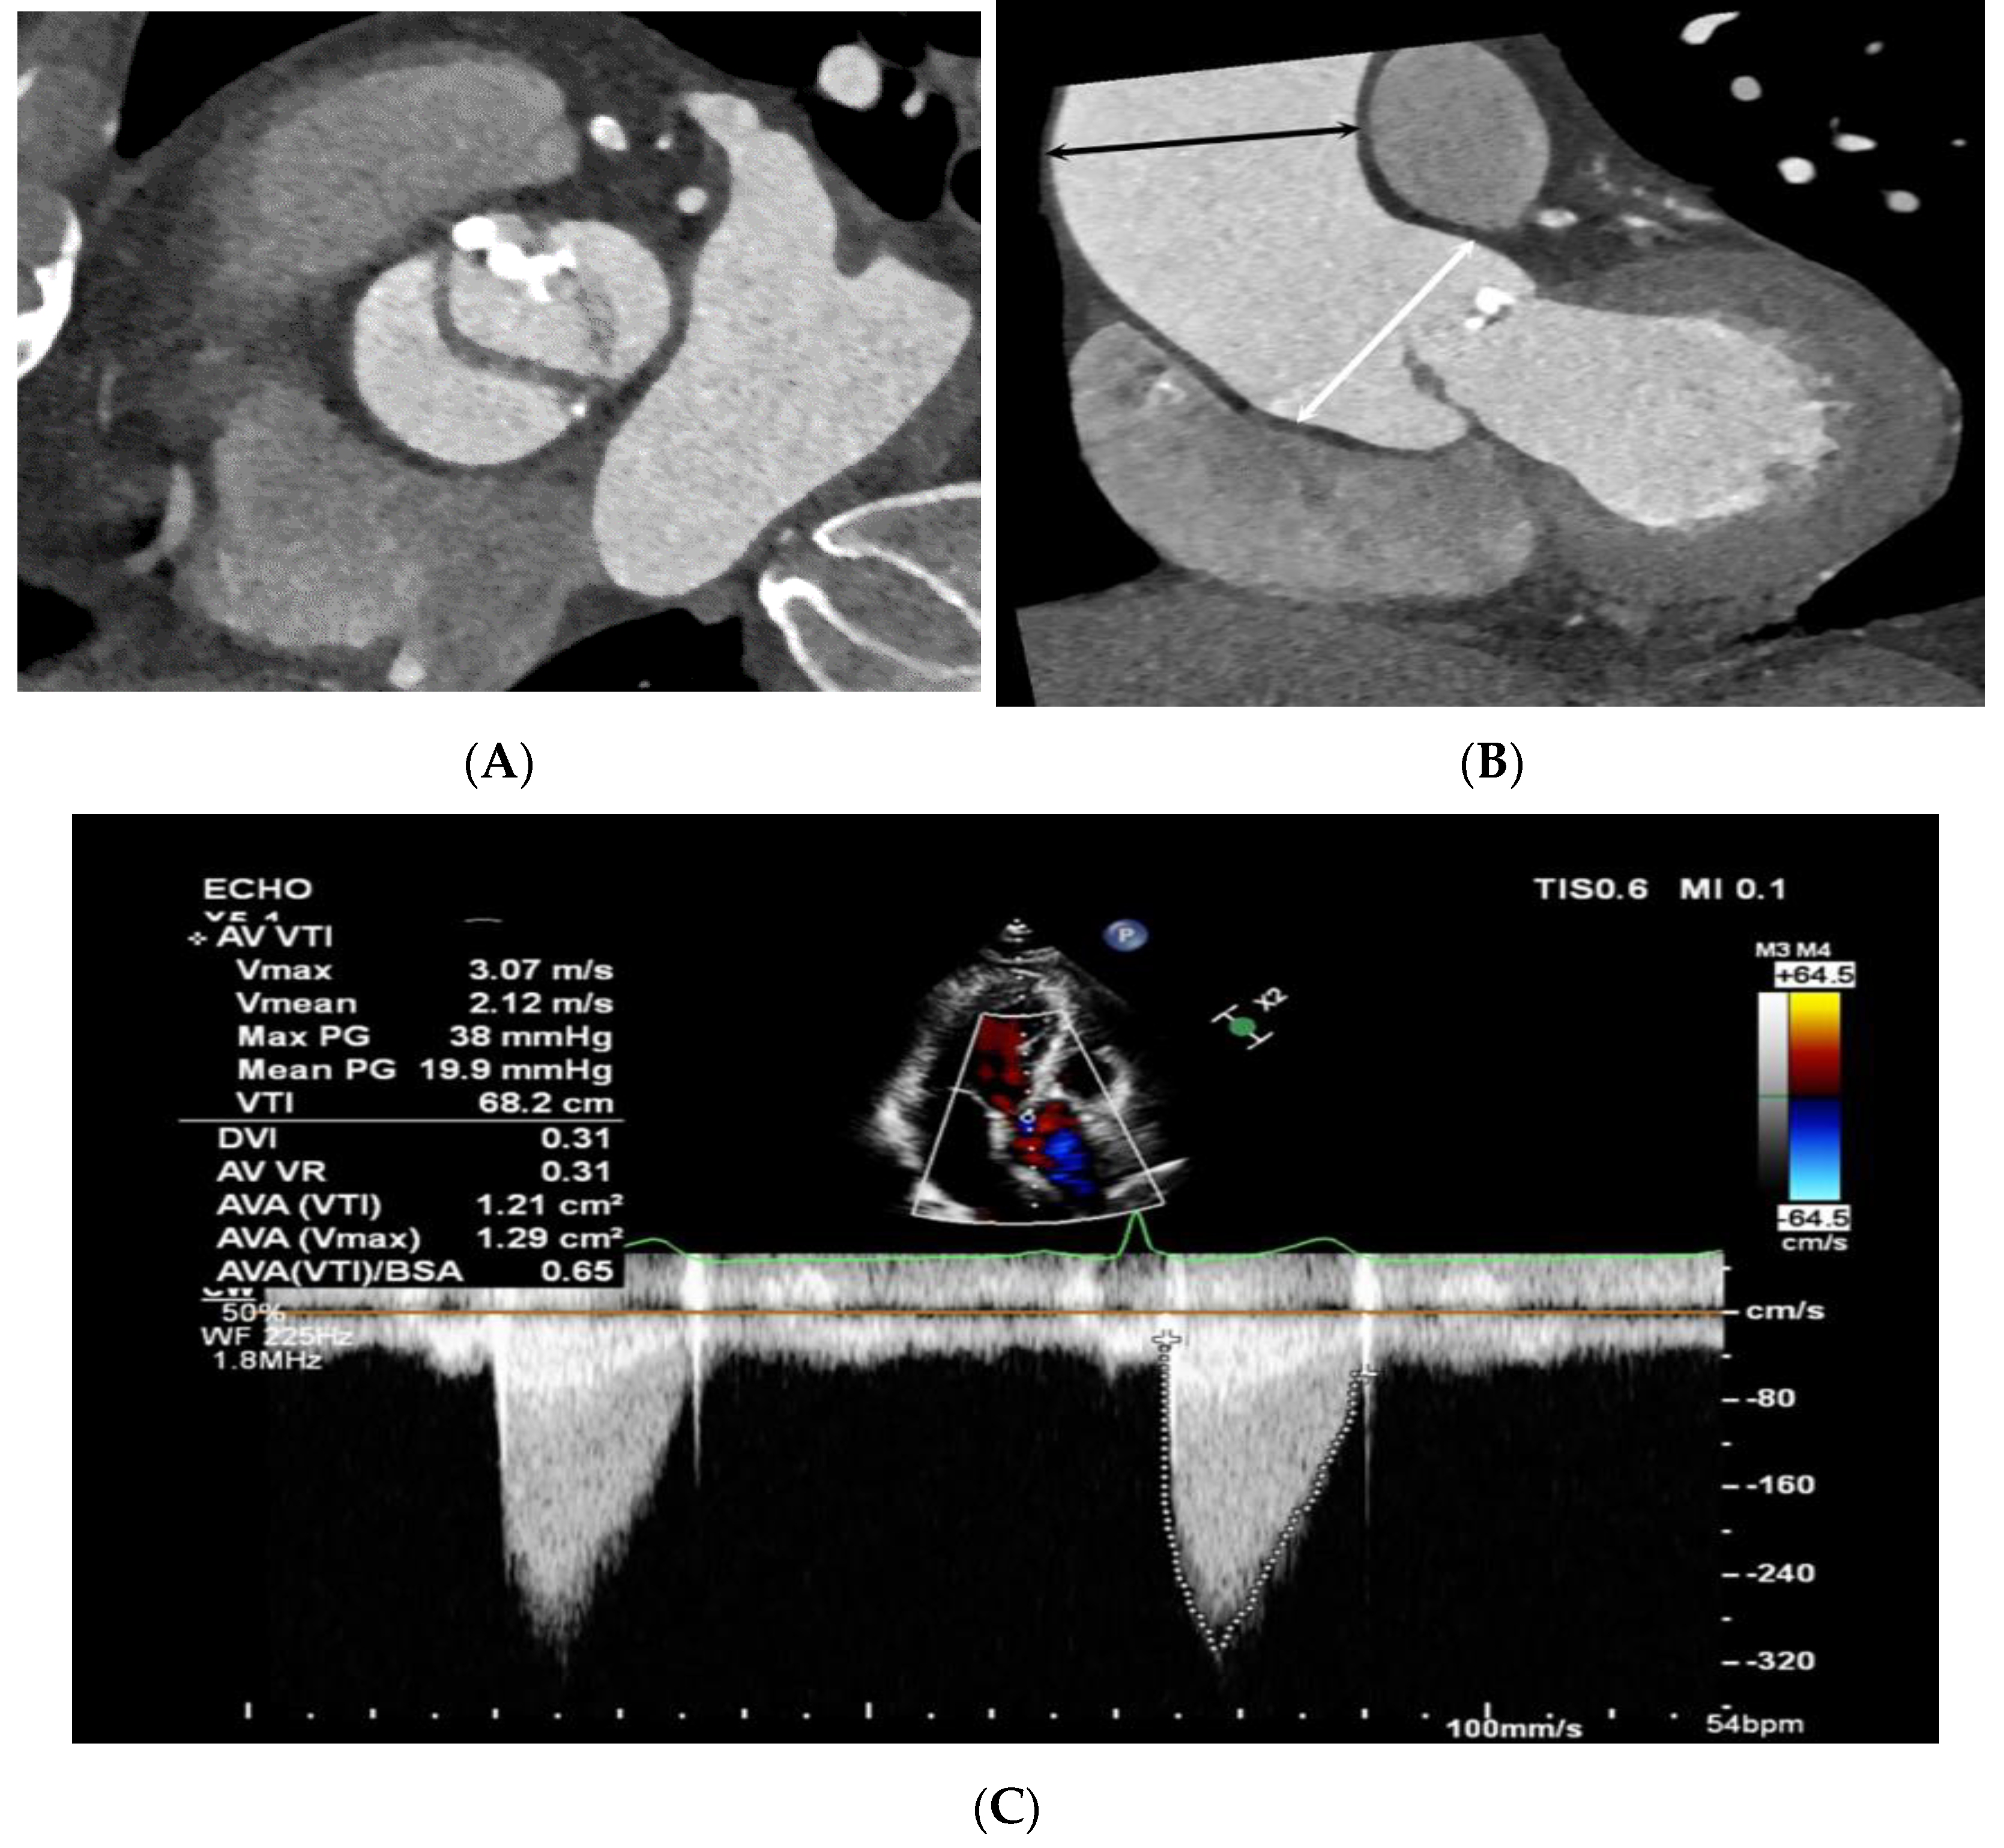

2.2. CT Imaging Protocols

2.3. CT Image Reconstruction and Analysis

2.4. Echocardiographic Evaluation